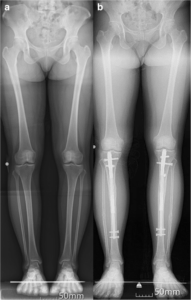

A correção de deformidades ósseas é um dos pilares da ortopedia reconstrutiva moderna e tem como objetivo restabelecer o alinhamento anatômico e funcional dos membros, corrigindo desvios angulares, rotações ou encurtamentos resultantes de condições congênitas, traumáticas ou adquiridas. No CBOT, utilizamos técnicas de osteotomia planejadas digitalmente em 3D, permitindo uma análise precisa da deformidade e uma execução cirúrgica milimétrica. O planejamento tridimensional possibilita prever o resultado final, minimizar erros intraoperatórios e otimizar o posicionamento dos segmentos ósseos.

Entre as principais tecnologias empregadas, destacam-se os fixadores externos hexapodais (como o Taylor Spatial Frame® e sistemas equivalentes), que possibilitam correções multiplanares de forma gradual, segura e controlada. Essas estruturas permitem ajustes pós-operatórios finos, guiados por software, otimizando o resultado funcional e estético.